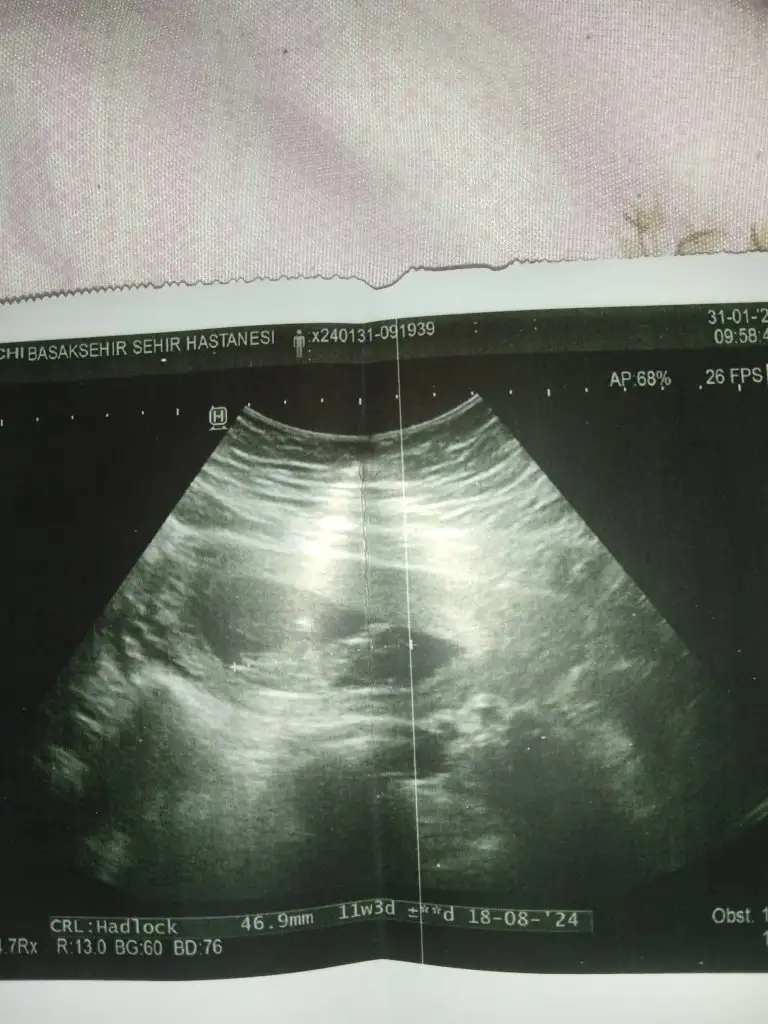

Buna da bakabilir misinizOglum ve kizimda ki ultrason görüntüsünden.

Oglum fotodaki gibiydi.

Kızımda göbek kısmı cok şişikti.

Ama tabi inşallah doğrudur. Yanılma payı her zaman %20 var…

Bi ayaklarını uzatmış ama, genelde yatarken toplu duşurta oluyorlar.Buna da bakabilir misiniz

Bence kız.

Tahminlerim doğru çıkarsa bana yazarmısınız